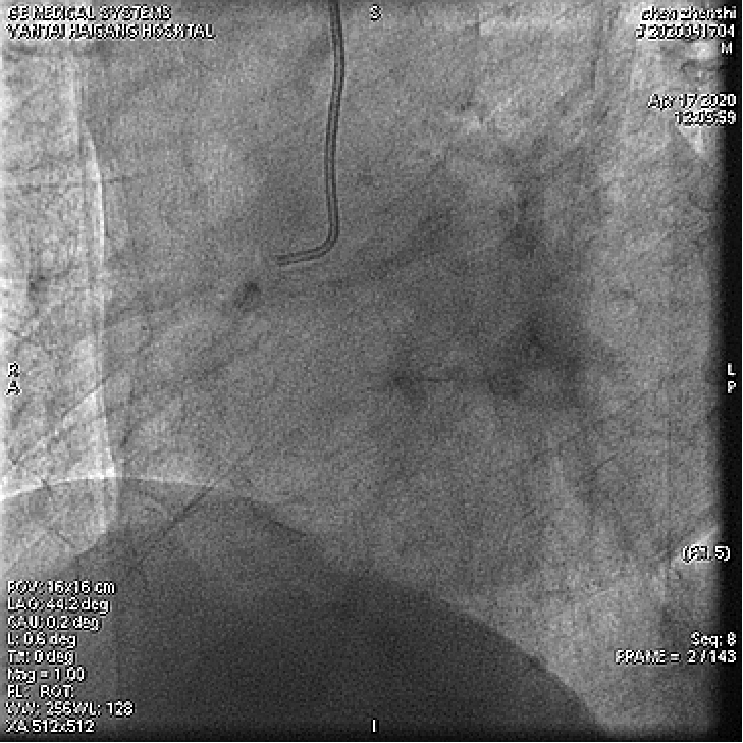

根据造影结果及患者病情 , 决定优先处理前降支病变 , 择期处理右冠;

分别送导丝至前降支及第一对角支 , 送2.0mm×15mm预扩球囊对病变部位进行充分预扩张处理 。

文章插图

于前降支中段、左主干-前降支近段依次置入PROMUS ELement 2.5mm×38mm、PROMUS Element3.0mm×38mm支架共2枚 。

复查造影前降支支架以远可见99%局限狭窄 , 于前降支远段置入Firebird 22.5mm×23mm支架1枚 , 并给予后扩张 。

患者手术过程中无明显不适症状 , 术后安返病房 。